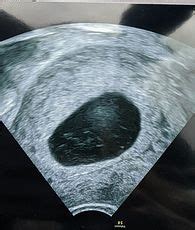

First things first, let’s clear up what a ‘missed miscarriage’ actually is. It’s not as common at the 20-week scan as it is in the earlier stages of pregnancy, but it’s good to understand the terminology. Basically, a missed miscarriage (also known as a silent miscarriage) is when the pregnancy has stopped developing, or the embryo or fetus has died, but your body hasn’t yet recognised this. This means you might not have any of the usual signs of miscarriage, like bleeding or cramping. Often, it’s only discovered during a routine check-up or an ultrasound scan, like the one you’ll have at 20 weeks. It’s a heartbreaking situation because, physically, your body might still be carrying the pregnancy, giving you no outward indication that anything is wrong. This is why the 20-week scan is so important – it’s a thorough check to ensure everything is progressing as it should be, and it can pick up on things that aren’t visible or palpable to you at home. The earlier stages of pregnancy are statistically where miscarriages are most common, typically before 12 weeks. However, the 20-week scan looks at a much wider range of fetal development and can identify issues that might not have been apparent earlier on, or sadly, conditions that have arisen more recently. It’s a crucial milestone, and while the focus is overwhelmingly positive, understanding the possibilities helps in managing any anxieties that arise.

Okay, so the big question: how common is a missed miscarriage specifically around the 20-week scan? This is where we can probably ease some minds. Missed miscarriages are not common at the 20-week anomaly scan. By 20 weeks, your pregnancy is considered well-established. Most early miscarriages happen in the first trimester, often before 12 weeks of pregnancy. The chances of experiencing a missed miscarriage at 20 weeks are significantly lower than in the early weeks. The 20-week scan is designed to look for structural abnormalities and developmental issues, rather than the cessation of fetal growth that defines a missed miscarriage. While the scan does check fetal viability (whether the baby is alive and well), the primary purpose shifts from confirming an ongoing pregnancy to detailed anatomical assessment. If a pregnancy has unfortunately ceased developing before 20 weeks, it’s more likely that the body would have expelled it naturally, or the missed miscarriage would have been detected in earlier check-ups or symptoms. The anomaly scan is thorough, and while it does screen for various potential problems, including some that could indicate a non-viable pregnancy, the event of a missed miscarriage at this specific stage is statistically rare. It’s more likely that if a missed miscarriage were to occur, it would have been identified much earlier. Therefore, while it’s understandable to have concerns, focusing on the overwhelming majority of positive outcomes at this scan is a healthier approach. The technology used allows sonographers to see a lot, and they are trained to spot any potential concerns, reassuring expectant parents when everything looks good. Remember, the odds are very much in your favour for a healthy, progressing pregnancy at this stage.

The 20-week scan, often called the anomaly or morphology scan, is a really important part of your antenatal care, guys. It’s not just about finding out the gender (though that’s a fun bonus for many!). This detailed ultrasound is designed to carefully examine the physical development of your baby. Sonographers will be looking at everything from the baby’s brain and heart to their kidneys and limbs, checking for any potential structural abnormalities or anomalies. They’ll measure different parts of the baby’s body to ensure they are growing at the expected rate and that everything is forming correctly. This scan is incredibly comprehensive. It helps to identify a wide range of potential conditions, some of which might require intervention shortly after birth, allowing medical teams to prepare and plan for your baby’s needs. Early detection means that you and your healthcare providers can make informed decisions and get the best possible care in place for you and your baby. For example, if a condition is found, you can be referred to specialists, and you’ll have the opportunity to discuss all the options and potential outcomes. This proactive approach is invaluable. It also provides reassurance. Seeing your baby healthy and developing well on the screen is incredibly comforting and can help to alleviate many of the anxieties that often accompany pregnancy. While the focus is on potential issues, the overwhelming majority of 20-week scans show healthy babies, offering immense peace of mind to expectant parents. The sonographers are highly skilled, and the equipment is sophisticated, making this a very informative and generally positive experience. It’s a key check-point in ensuring your pregnancy is progressing smoothly and that your baby is on track for a healthy arrival.

So, what actually happens during your 20-week scan? You’ll usually lie down on an examination bed, and a sonographer will apply a clear, warm gel to your abdomen. This gel helps the ultrasound probe (a transducer) to slide smoothly over your skin and transmit clear sound waves. The probe is then moved gently across your belly, and the ultrasound waves create images of your baby on a monitor. The sonographer will systematically examine different parts of your baby’s body. They’ll measure the baby’s head, abdomen, and thigh bone, check the spine, heart, brain, kidneys, stomach, and bladder, and look at the placenta and the amount of amniotic fluid. They’ll also check the umbilical cord. You’ll likely see your baby moving around, maybe kicking or stretching! It’s a pretty amazing experience. You’ll have the opportunity to ask questions during the scan, and the sonographer will explain what they are seeing. If they identify anything that concerns them, they will discuss it with you and explain the next steps, which might involve further scans or consultations with a specialist. Try to relax and enjoy seeing your little one. Deep breaths can help if you’re feeling anxious. Remember that the sonographer is a trained professional whose job is to conduct this thorough examination. They will provide you with clear information about what they find. Sometimes, it can be a little tricky to get a clear view of certain parts of the baby, especially if they are in an awkward position or if there’s a lot of movement. The sonographer might ask you to move around, cough, or even have a sugary drink to encourage the baby to shift position. It’s all part of the process to get the best possible images for a comprehensive assessment. The entire process usually takes between 20 to 40 minutes, depending on how cooperative the baby is!